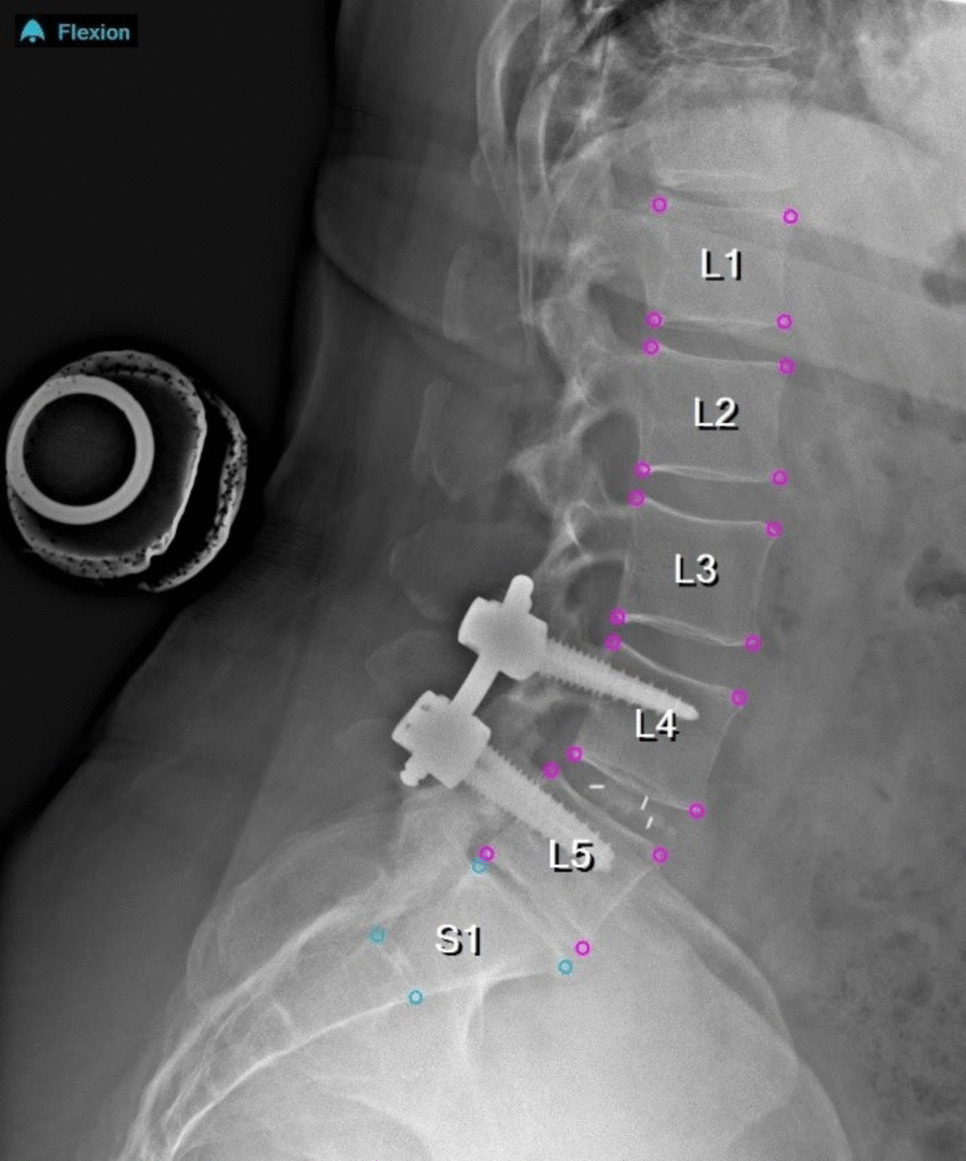

Investigating the Effects of Image Scaling Techniques in Radiographic Measurements of Spinal Alignment and Motion: A Comparative Analysis

Radiographic measurements from spinal radiographs are crucial in many diagnostic and therapeutic decisions. However, widel...